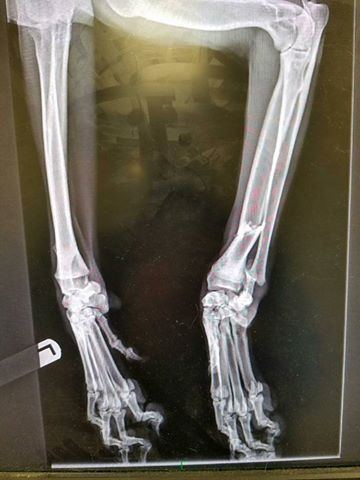

This is the where my leg was broken, both bones were broken clean through on my right leg.   The toes are fine, I am laying on my side for the x-ray on the left.